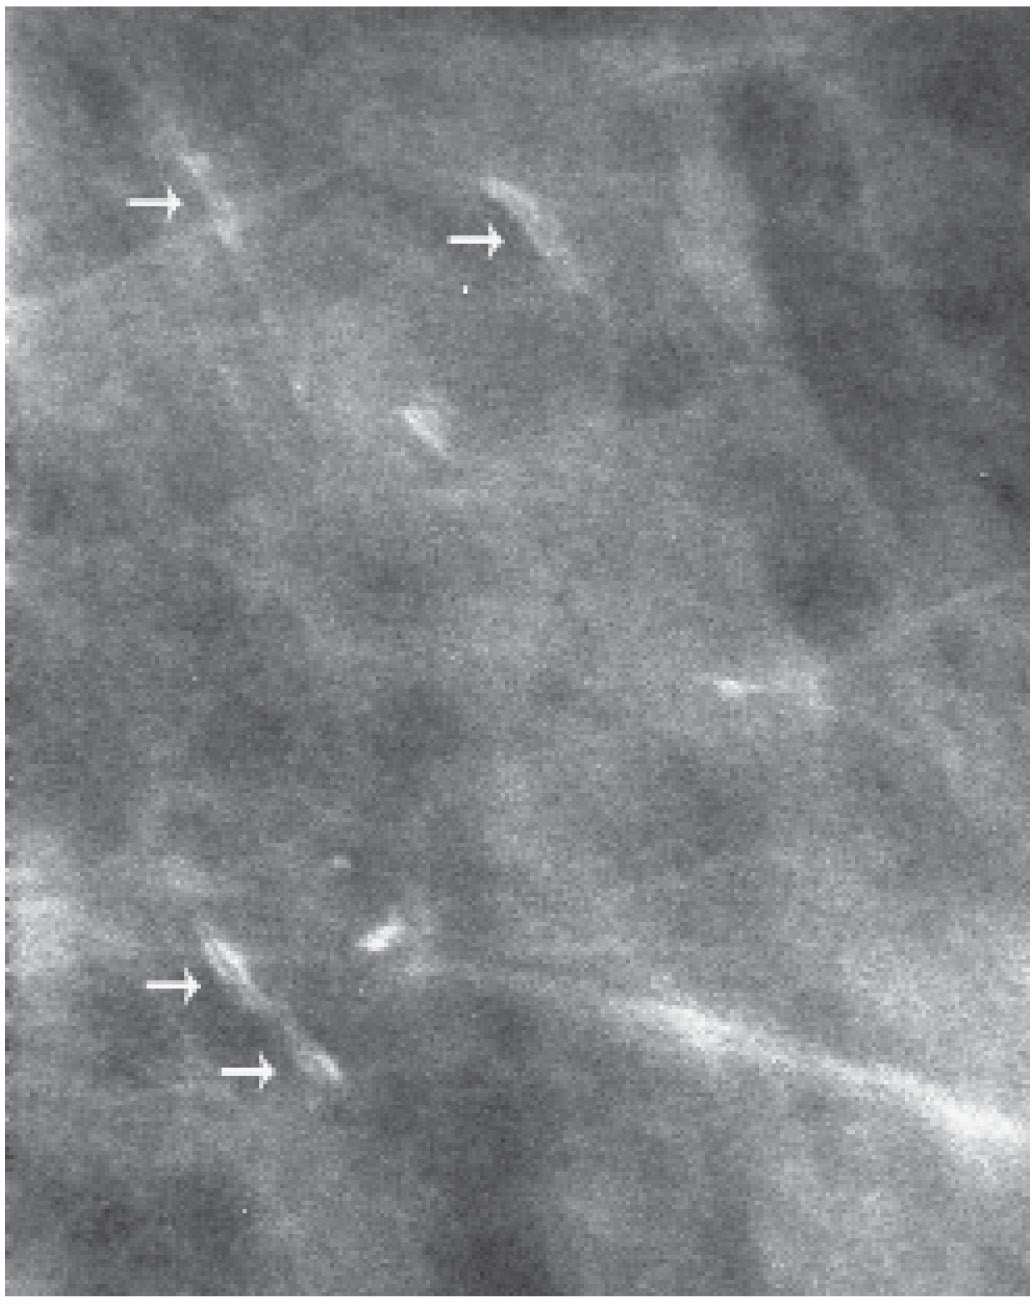

Intraductal carcinoma of the breast with calcium deposit (arrows What Do Calcium Deposits In The Breast Mean They’re common and often show up on a routine. These white spots that appear are actually small pieces of calcium that have been deposited in your breast. Breast calcifications are common on mammograms, and they're especially prevalent after age 50. Breast calcifications are calcium deposits that develop in breast tissue. Calcifications are small deposits of calcium that show up on. What Do Calcium Deposits In The Breast Mean.